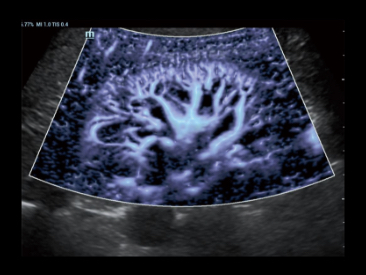

Glazing Flow

Совершенно новый способ продемонстрировать 2D цвет/мощность, инновационный доплеровский поток в 3D- визуализации.

Glazing Flow обеспечивает четкую визуализацию структуры дугообразной артерии и малой междольковой артерии с трехмерным изображением.